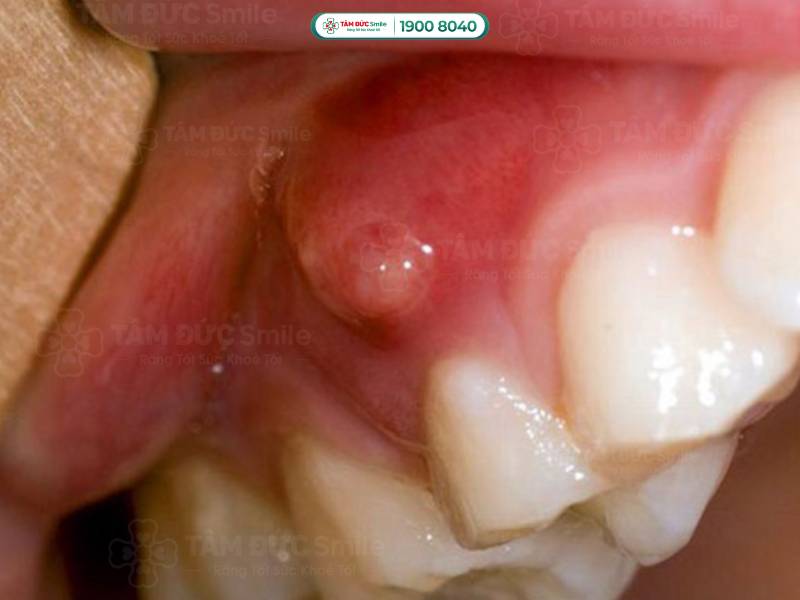

1.1.2. Áp xe chóp răng (áp xe chân răng)

Áp xe được hiểu là tập hợp mủ được hình thành từ các tế bào bạch cầu chết, vi khuẩn và những mảnh mô vụn. Vấn đề áp xe chóp răng bắt đầu từ tủy răng và kết thúc ở phần chóp chân răng.

Vấn đề áp xe chóp răng bắt đầu từ tủy răng và kết thúc ở phần chóp chân răng

Chứng áp xe chóp răng thường khó nhận biết bằng mắt thường. Người bệnh có những biểu hiện dưới đây nên đến thăm khám ở các cơ sở y tế để được chẩn trị chính xác:

- Đau nhức răng, người bệnh chỉ cần nhai nhẹ cũng có cảm giác đau.

- Ê buốt răng khi sử dụng các loại thực phẩm nóng, lạnh.

- Vùng áp xe có thể làm hành sốt, nổi hạch ở cổ, khiến người bị mệt mỏi.

- Phần lợi dưới chân răng bị sưng; khi soi gương, bạn có thể thấy hạt mủ tụ ở phần chân răng gây đau.